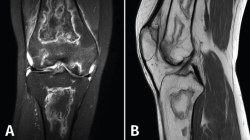

Figura 52. A: corte de secuencia coronal T2 Fat-Sat con infartos óseos en el fémur y la tibia; B: corte de secuencia sagital T1 con infartos óseos en el fémur y la tibia.